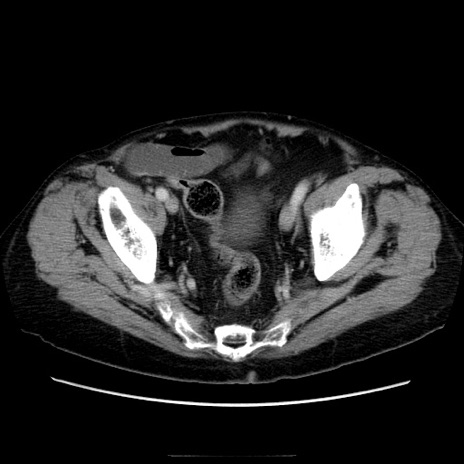

症例21(横断像)

【症例】70歳代男性

【主訴】腹痛

【現病歴】肝硬変・肝細胞癌にてかかりつけの方。約9時間前に食後より腹痛出現。症状が徐々に増悪し、嘔吐出現したため来院。

【既往歴】肝硬変、肝細胞癌(RFA、TACE後)

【身体所見】意識清明、表情苦悶様、BT 36℃、BP 129/78mmHg、P 88bpm、SpO2 97%(RA)、右上腹部から心窩部にかけて圧痛あり、反跳痛なし、筋性防御あり。

【データ】WBC 5800、CRP 0.16